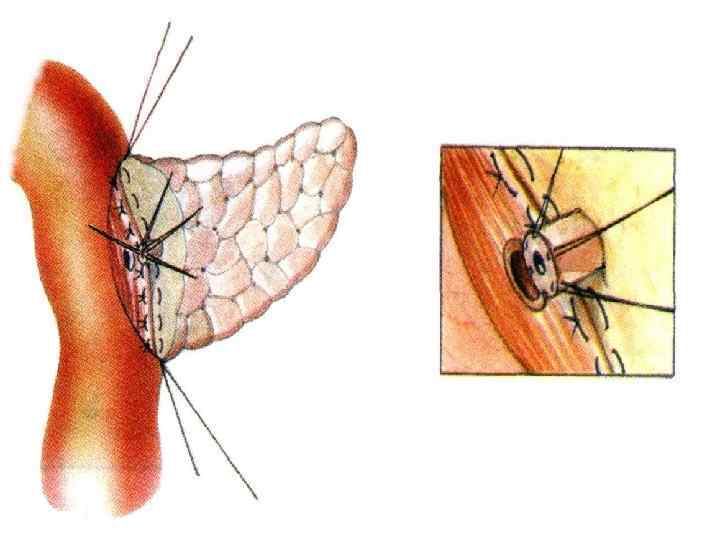

Резекция чревного ствола и общей печёночной артерии при выполнении ДСРПЖ Вид резекции Циркулярная резекция чревного ствола Всего Число больных с пластикой 4 без пластики 11 15